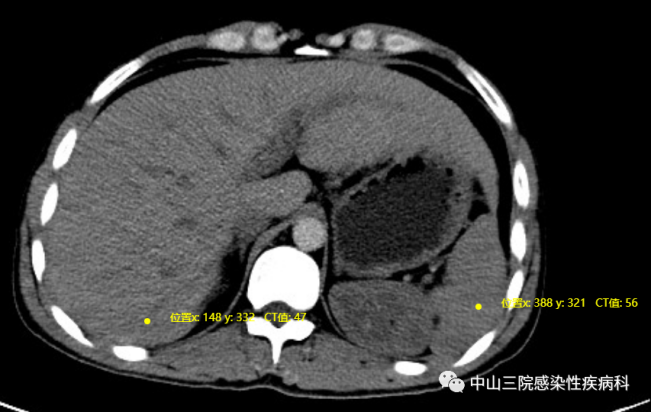

图4.腹部CT未见肝硬化或脾大,肝脏密度弥漫性降低(图源:中山三院感染科)

随后小何的血尿质谱与基因检测结果出来,佐证了李教授的诊断:

尿质谱分析:乳糖尿伴轻度糖尿,丝氨酸及苏氨酸比例颠倒;

血质谱分析:瓜氨酸、谷氨酰胺、鸟氨酸、脯氨酸、丝氨酸、异戊烯酰基肉碱升高;

遗传肝病相关基因组测序:存在SLC25A13 7q21.3 NM_014251.2 Exon9 c.853_855delTATG p. (Met285fs) 纯合突变。